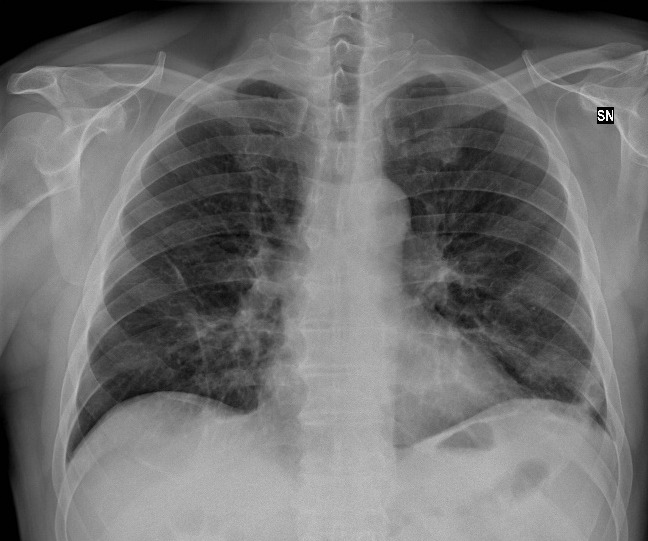

In the 33 (69.3%) of the cases with both a chest CT and a chest radiograph, the radiograph showed signs of COVID-19 (Figure 3). Most chest radiographs had non-specific findings, with the most common findings noted as hypotransparency (i.e., mild opacity in an area that should be transparent) or the radiologist documenting that the chest x-ray was consistent with COVID-19 without further detail. A total of 46 (97.8%) of the sample cases showed bilateral lung findings consistent with COVID-19 on CT. One (2.1%) patient x-ray showed only unilateral findings, with ground glass opacities being found in the left lung only. (Figure 4)

One (2.1%) sample patient tested negative via nasal swab for COVID-19, but continued symptoms led to a physician ordering a chest CT, which showed bilateral ground glass opacities; this led to a second swab, which was positive for COVID-19. Both figures 5 and 6 are from this patient, showing a chest radiograph that the radiologist deemed negative and a chest CT that was deemed by a radiologist to have positive findings which is what led to a second nasal swab. (Figures 5 and 6)